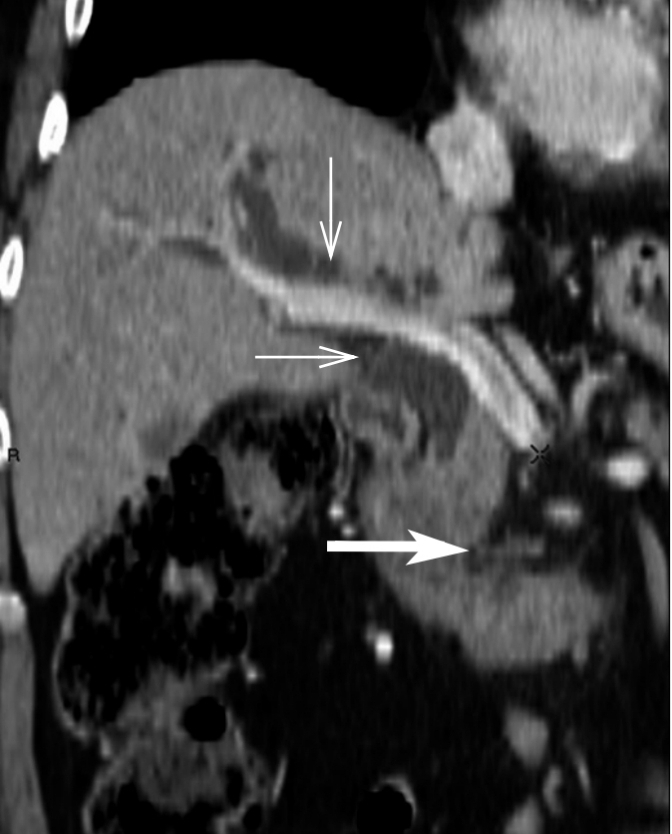

Cholangiocarcinome du cholédoque détecter sur un cholangio-IRM.

Publié par : Kamal nadifi

TDM abdominale avec injection en coupe axiale

Publié par : Kamal nadifi

TDM abdominale avec injection en coupe coronale.

Publié par : Kamal nadifi